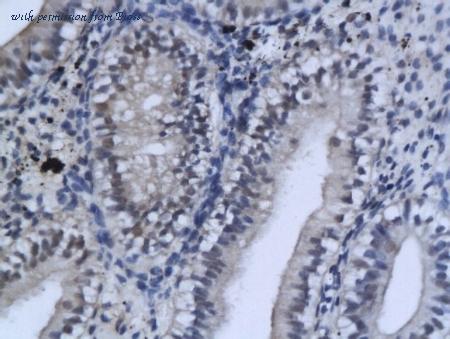

information sur le gène - rat Gsk3b

- synonyme:glycogen synthase kinase-3 beta; GSK-3 beta; factor A; serine/threonine-protein kinase GSK3B

- description:glycogen synthase kinase 3 beta